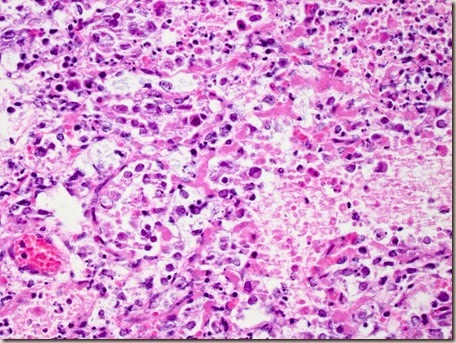

Dal punto di vista istopatologico, è possibile distinguere due tipi di stomatite cronica erosivo-ulcerativa: il primo, caratterizzato da denso infiltrato di linfociti e plasmacellule nella sottomucosa, il secondo, caratterizzato invece da infiammazione cronica attiva, con presenza di neutrofili della mucosa e sottomucosa. Spesso è interessato anche l'osso alveolare, che mostra infiltrato infiammatorio misto ad alterazioni litiche della struttura.